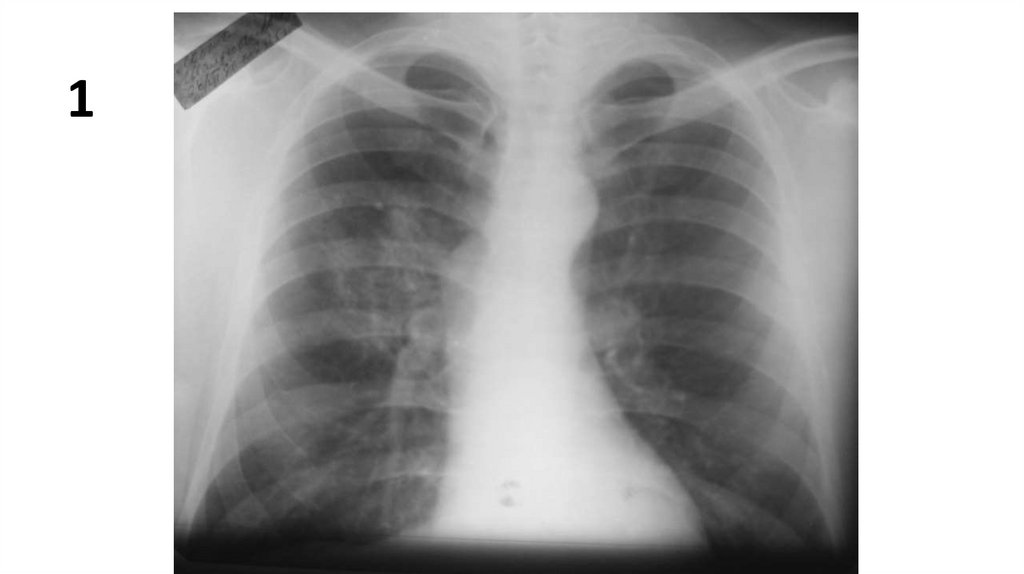

1

3.